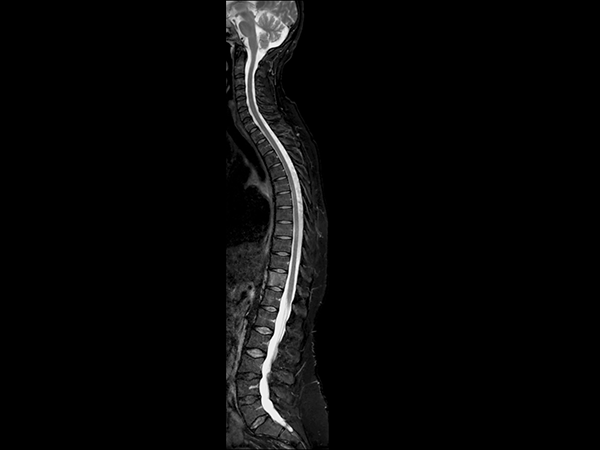

Total Spine with mDIXON XD TSE

Aarhus University Hospital, Denmark

Patient with known breast cancer and bone metastates. After six series of treatment this patient was referred to MRI. Total spine T2W mDIXON TSE and T1W TSE imaging was done in two stations to visualize the metastasis in Th11. Excellent fat suppression is seen, including the neck region. Only one mDIXON TSE scan provides images with and without fat suppression and thus saves almost half the time compared to traditional imaging.